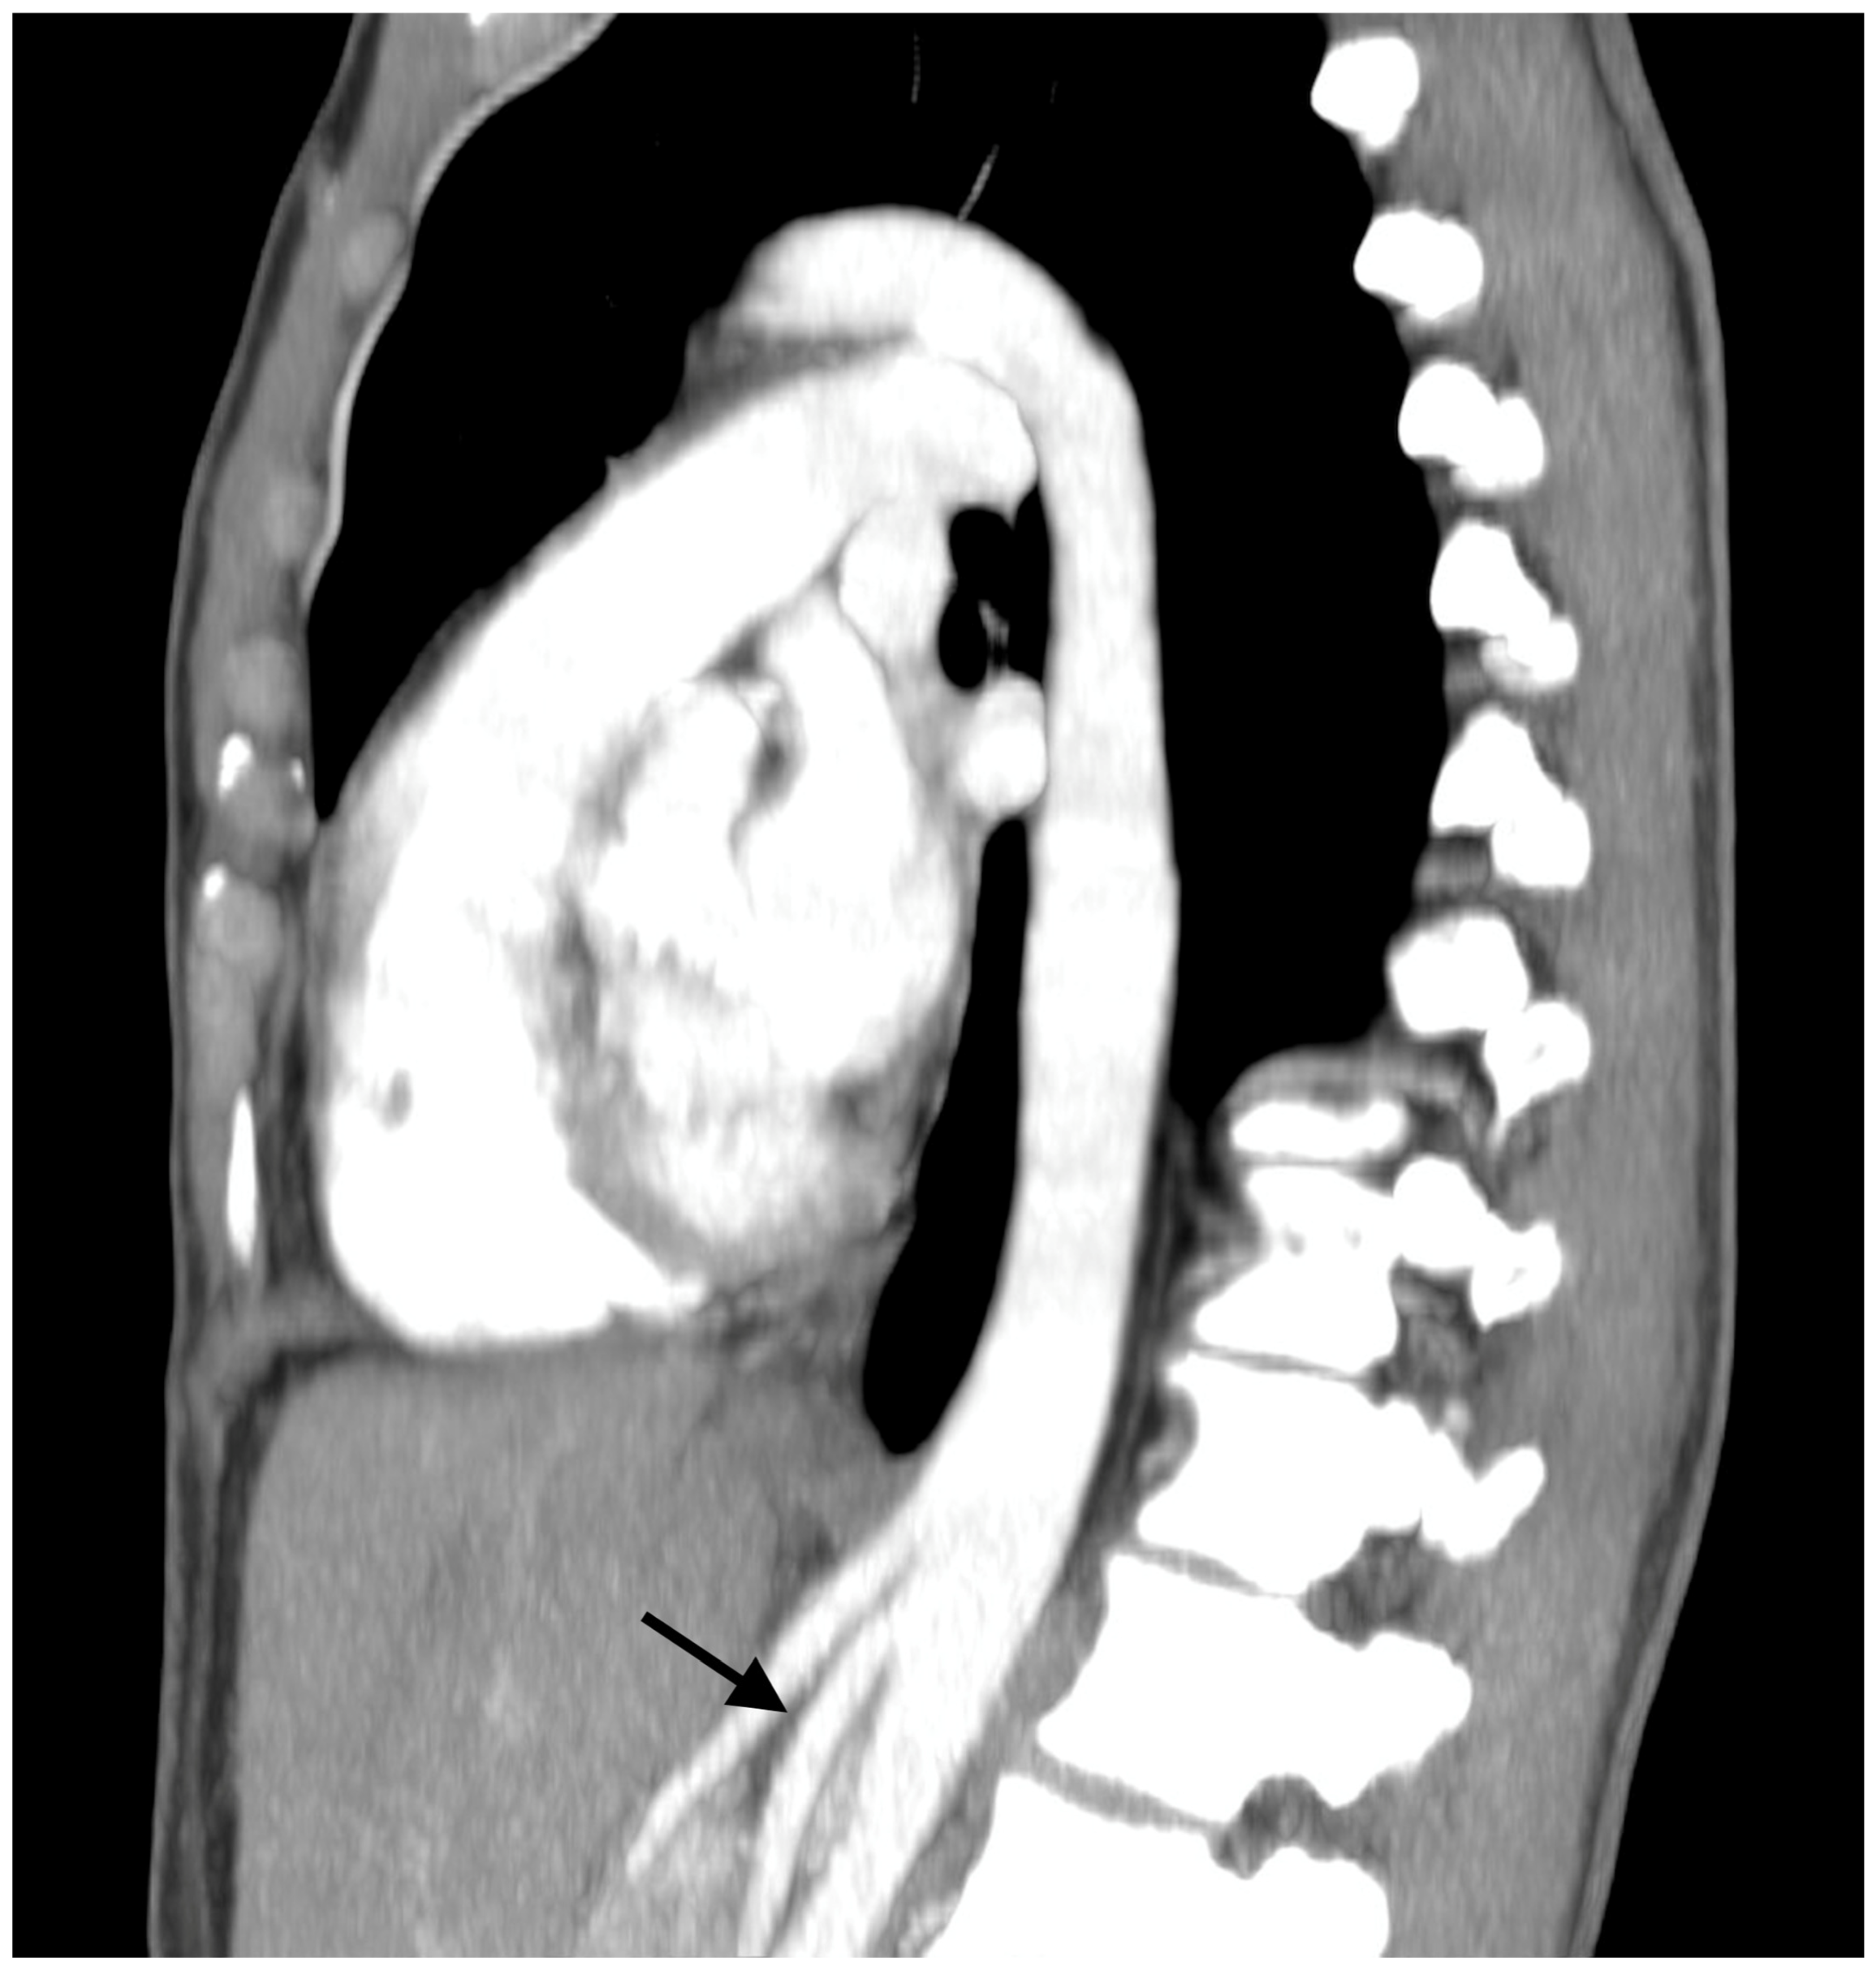

Nutcracker Syndrome as an Uncommon Cause of Isolated Hematuria in Adults

Case Presentation